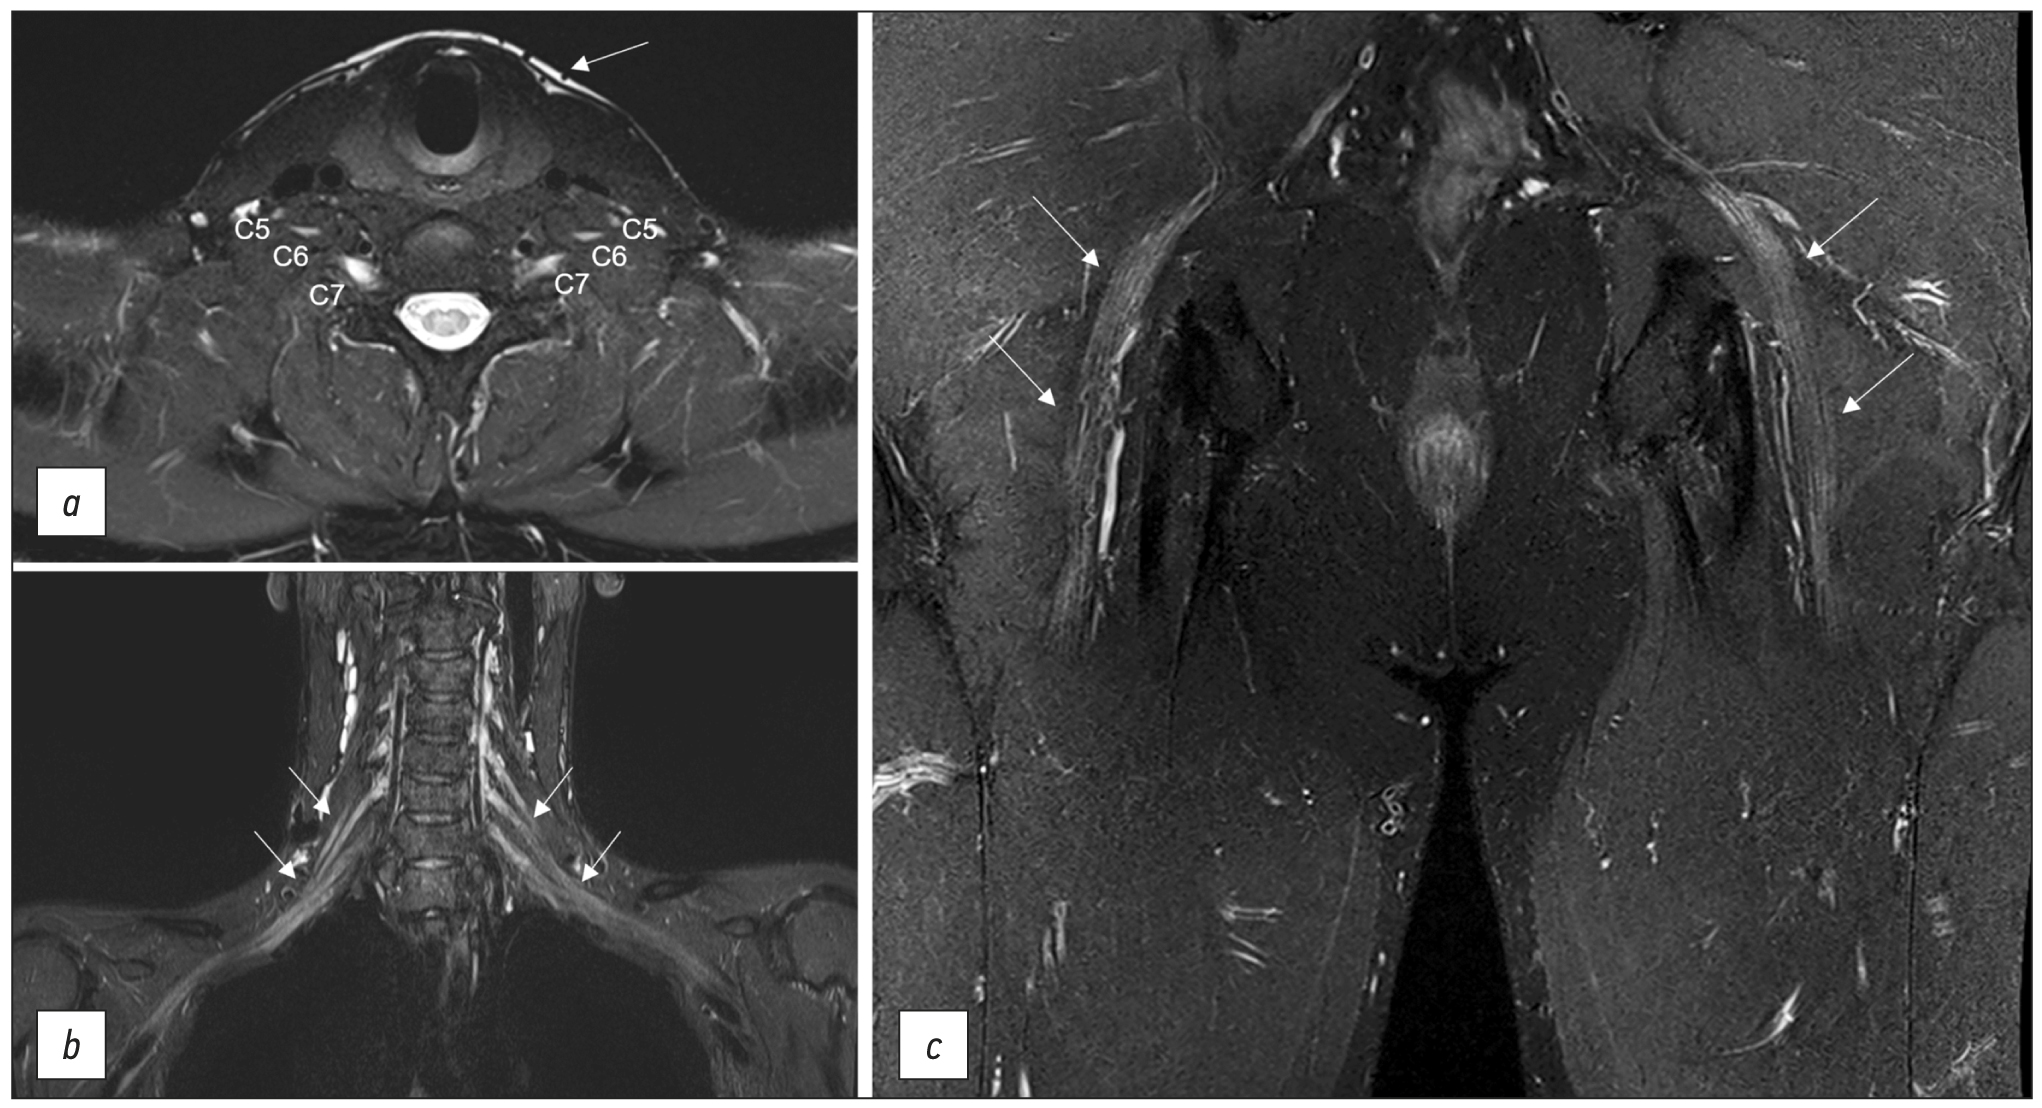

Early observations showed that T2 images are the most important for diagnosing peripheral nerve injuries [31]. Non-fat-suppressed sequences, typically 2D, are useful for observing the epineurium (Fig. 2). Fat suppression differentiates the relatively high nerve signal and the surrounding fat tissue. For T2-weighted images without fat suppression, the recommended echo time is >90 ms (milliseconds), ideally 100–105 ms. For fat-suppressed sequences, it can be reduced to 60–80 ms. The latter, so-called fluid-sensitive images, provide ideal nerve visualization (Fig. 3) with increased signals in the area of pathological changes [32]. Fat suppression strategies are based on the difference in water–fat precession frequency and fat tissue having a longer T2 relaxation time and shorter T1 relaxation time than muscle tissue or nerve fibers [2].

Fig. 3. Various techniques of fat suppression for magnetic resonance imaging: (a) brachial plexuses in T2-FatSat mode, an axial projection: the anterior branches of C5, C6, and C7 spinal nerves are noted, without abnormalities, with a slightly increased signal; heterogeneous fat suppression with unsatisfactory signal along the periphery of the area of interest (arrowed); (b) brachial plexuses in STIR mode, a coronal projection: homogenous fat suppression throughout the entire field of view, typical elements of brachial plexuses with a slightly increased signal (arrowed); and (c) sciatic nerves in T2-Dixon mode, a coronal projection: homogenous fat suppression, normal sciatic nerves with a slightly increased MR signal (arrowed).

The required fat suppression can be performed by spectrally selective fat suppression (FatSat) in T2-weighted spin echo sequences with high contrast, nearly no pulsation artifacts, and reduced magnetic susceptibility artifacts [33]. However, if there are metal structures in the field of vision, this technique should be avoided. The main disadvantage is poor fat suppression away from the center of the field of view or inhomogeneous fat suppression along the curves of the body [25].

Short-TI inversion recovery (STIR, where TI is the inversion time in milliseconds) provides excellent homogeneous fat suppression at various levels of magnetic induction and field homogeneity, but it is nonselective (it suppresses signal from all, not only fat, tissues with short T1). It cannot be used following intravenous contrast enhancement (as this sequence sums T2 and T1 contrast, providing only T2-weighted images). In many circumstances, it is susceptible to pulsation artifacts, erroneous nerve signal augmentation due to increased signal from intraneural fluid, and a low signal-to-noise ratio. Therefore, this sequence is more commonly used for plexus visualization, where spectrally selective fat suppression is ineffective for a variety of reasons, including the presence of metal in the field of view, using various modifications, such as shorter echo time (30–40 ms), a greater number of echo times, and a wider transmission frequency (400–500 Hz/Px).

T2 SPAIR (T2-weighted SPectral Attenuated Inversion Recovery), a combination of FatSat and STIR techniques, is the best sequence for extremity MR neurography because it suppresses fat signals similarly to STIR, but it is more selective in the center and periphery of the field of view with higher SNR and fewer pulsation artifacts. The signal from a normal nerve usually is isointense to the signal from skeletal muscle on T2-SPAIR images. Depending on the user’s preferences, weak and strong contrast types are available, with the weak giving higher signal homogeneity and the strong providing greater isointensity of the nerve signal. The main disadvantage of this sequence is the possibility of poor fat suppression in some edge slices, particularly along the scanning area’s boundary, and the inability to use this technique with low-field devices and significant magnetic field inhomogeneity. Although T2-SPAIR is less sensitive to metal artifacts than frequency-selective fat suppression sequences, the STIR sequence should still be used if the metal is in the scanning area.

The Dixon approach achieves optimal fat suppression, but image quality may be reduced from the central scanning area [25]. Thomas Dixon proposed this approach in 1984 [34]. The chemical shift effect was predicated on a difference in the resonance frequency of fat and water protons. A two-echo sequence is used. Water and fat signals occur in-phase and antiphase during the first and second echo times. Dixon demonstrated that additional images can be computationally created based on these images with simply the water signal (dixonW) and the fat signal (dixonF). The fat signal is suppressed in dixonW images. These images are commonly used in clinical practice because they provide homogeneous fat suppression, and the only notable artifact is a fat–water exchange caused by magnetic field inhomogeneity, which occurs frequently around the coil coverage area’s border [35]. However, due to the long scanning time, the use of this neurography technique is limited to 2D imaging.